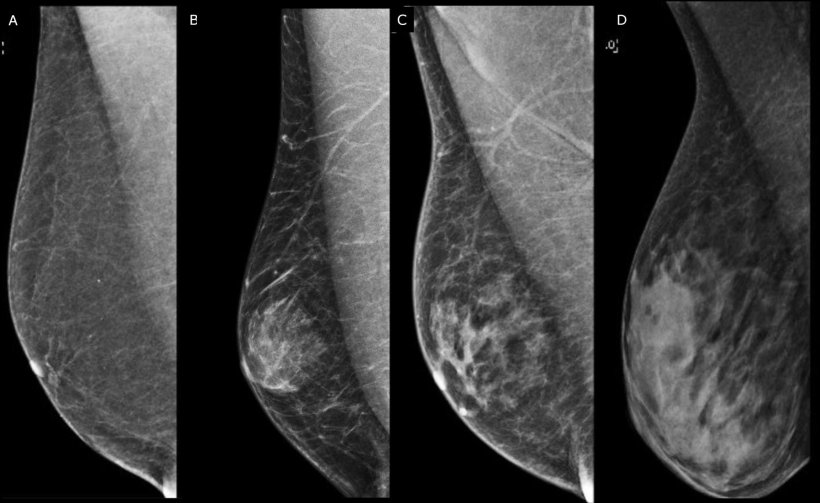

Image source: D’Angelo A, Portaluri A, Caprini F et al.: Male Breast: A Review of the Literature and Current State of the Art of Diagnostic Imaging Work-Up; Diagnostics 2023 (CC BY 4.0)

The EUSOBI survey on male breast cancer was sent to breast imagers across Europe and received 825 responses – mostly from radiologists – across 34 countries. While the ACR and UK guidelines offer advice on use of ultrasound, mammograms or digital breast tomosynthesis (DBT) for men, survey respondents indicated varied approaches.

Many practitioners perform ultrasound for initial imaging in benign indeterminate palpable masses for men under 25, and mammogram or DBT for men over 50. For suspicious palpable masses, the vast majority (82%) use ultrasound for patients under 25 and a combination of mammogram or DBT for those over 50.

The survey also explored clinical approaches to gynecomastia and pseudo-gynecomastia. 'In younger populations, it is ultrasound and over 50 it is mammogram or DBT, while 72% of respondents said they did imaging for both unilateral and bilateral gynecomastia,' Healy reported.